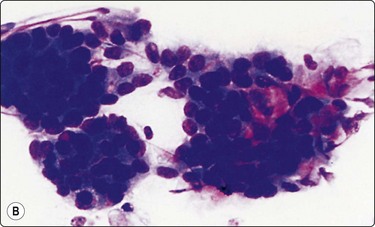

Fig. 4.9 Nasopharyngeal carcinoma (undifferentiated, lymphoepithelial type, WHO type III)

Loose clusters of undifferentiated epithelial cells with vesicular nuclei, prominent nucleoli and pale fragile cytoplasm. Background of lymphocytes. (A, MGG, HP; B, H&E, HP).

Criteria for diagnosis (undifferentiated carcinoma nasopharyngeal type (UCNT)/WHO type III/lymphoepithelial carcinoma)

Undifferentiated malignant cells, single and in clusters,

Variable amount of pale, fragile cytoplasm,

Large vesicular nuclei with prominent central nucleoli,

Admixture with, and background of, lymphoid cells, often with prominent plasma cells,

Ancillary tests: neoplastic cells positive for cytokeratin, negative for lymphocyte markers. EBV-associated nuclear antigen.

Nasopharyngeal carcinoma (NPC) is a clinicopathologic entity different from other squamous cell carcinomata of the head and neck. It is distinguished by its particular histology, geographic distribution, relationship to Epstein-Barr virus, and the absence of an alcohol or tobacco etiological relationship. A proportion of NPCs show squamous differentiation and the cytological pattern of non-keratinizing squamous cell carcinoma (squamous cell carcinoma/WHO type II) (Fig. 4.8). Keratinized cells (WHO type I) are uncommonly found. The majority of NPC are poorly differentiated or undifferentiated. Cells from undifferentiated NPC (UCNT, WHO type III) form loose clusters with no specific microarchitectural pattern, and are usually mixed with lymphoid cells. In the ‘lymphoepitheliomatous’ type (Schmincke-Regaud) the cells tend to be less cohesive, resembling Hodgkin’s disease or large cell non-Hodgkin lymphoma. However, in NPC, the malignant cells are still clustered and have more abundant pale cytoplasm contrasting with the lymphoid cells in the background (Fig. 4.9). Plasma cells are frequently found among the lymphoid cells. Immunostaining for cytokeratin and a pan-lymphocyte marker is helpful. Epstein-Barr virus-associated nuclear antigen is demonstrable by anticomplement immunofluorescence in undifferentiated tumors. Other patterns of growth may occur and may cause diagnostic problems; for example, spindle cell forms may be difficult to recognize as carcinoma.